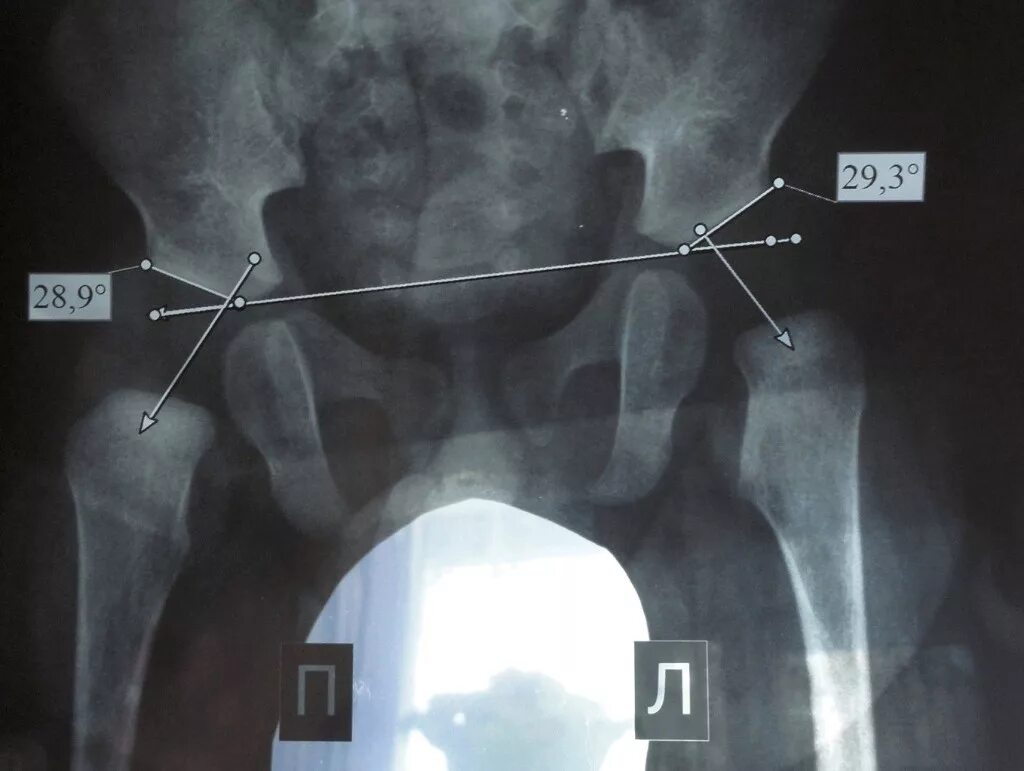

Лимбус тазобедренного сустава это